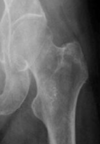

Subcapital fracture (intracapsular)

Intracapsular (Garden classification)

Intracapsular NOF fracture Garden classification type I